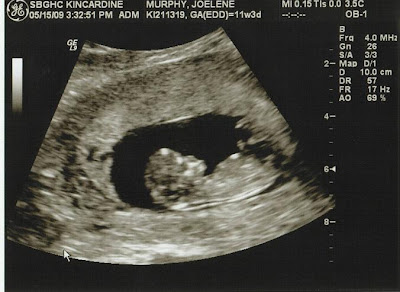

I had my second ultrasound on May 15th and Matt got to come and see BabyMurphy wiggling around! S/he was really moving quite a bit, but we got to see some great shots and bring one home as well...

BabyMurphy isn't just a legume anymore! So cute!